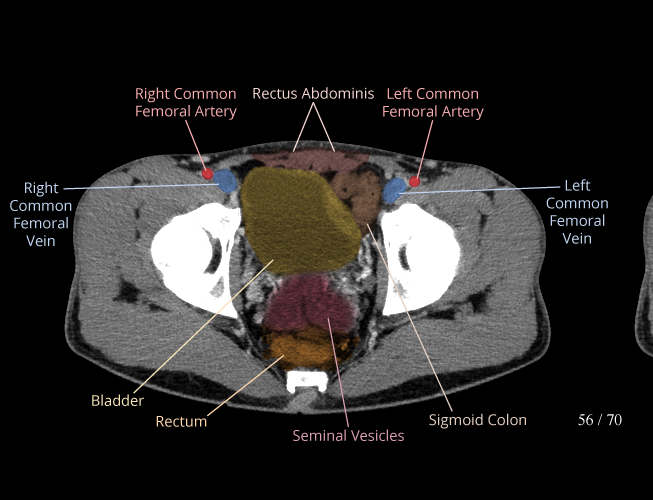

Pelvis

Covers pelvic MRI anatomy.